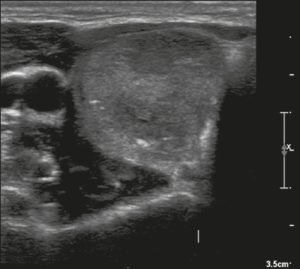

Ở đây, chúng tôi cung cấp các ví dụ minh họa việc áp dụng thực tế hệ thống ACR TI-RADS (Hình 18, 19, 20, 21). Các chú thích dưới hình mô tả chi tiết các mục đã được đánh giá và hiển thị điểm số trong ngoặc đơn.

Hình 20. Hình ảnh nhân giáp hỗn hợp đặc và nang (1 điểm), đồng âm (1 điểm), rộng hơn cao (0 điểm), và lan rộng ra ngoài giới hạn phía trước của tuyến giáp (3 điểm), không có các ổ tăng âm hay bóng lưng (0 điểm). Do đó, tổng điểm là 5 điểm và mức độ nguy cơ được phân loại là TR4.